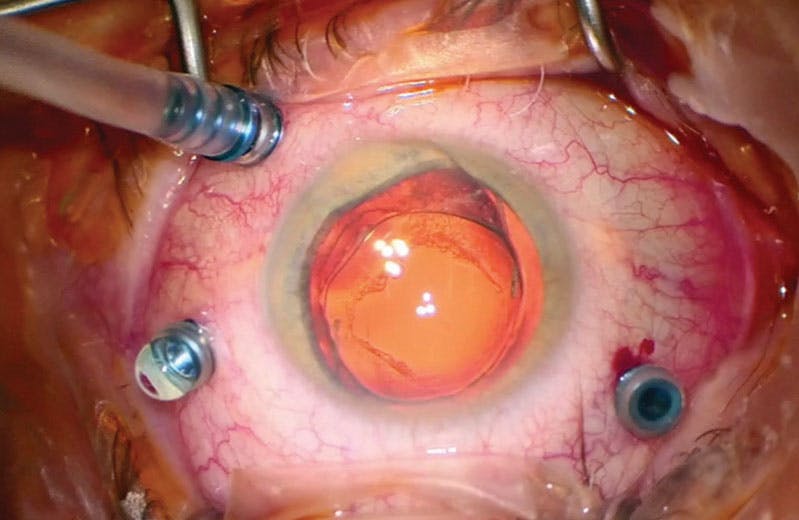

As his visual acuity deteriorated along with worsening macular schisis, the patient underwent PPV with ILM and ERM peeling with myopic forceps after brilliant blue G dye staining (Video and Figure 2A). The post-ILM peeling intraoperative OCT showed an immediate decrease in retinal thickness (Figure 2B).

<p>Figure 2. The patient underwent ILM peeling with brilliant blue G dye staining (A). Intraoperative OCT immediately after membrane peeling showed decreased retinal thickness (B).</p>

Figure 2. The patient underwent ILM peeling with brilliant blue G dye staining (A). Intraoperative OCT immediately after membrane peeling showed decreased retinal thickness (B).